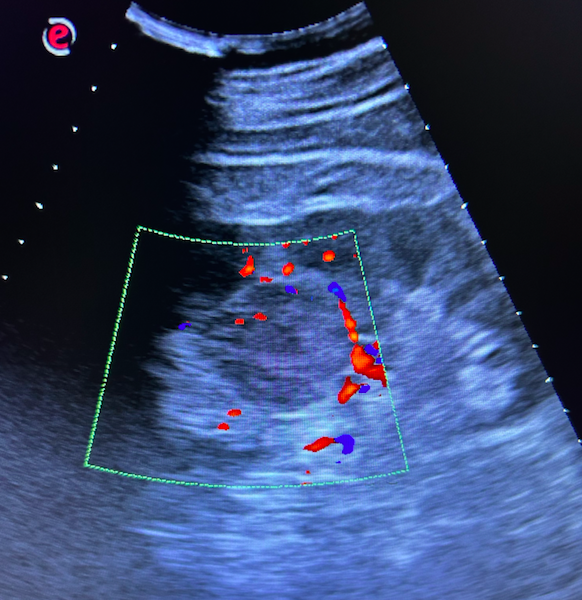

Riñones sin datos de hidronefrosis o litiasis pero en riñón izdo se visualiza lesión levemente hipoecogénica respecto a médula renal, de bordes bien definidos con doppler positivo en periferia.